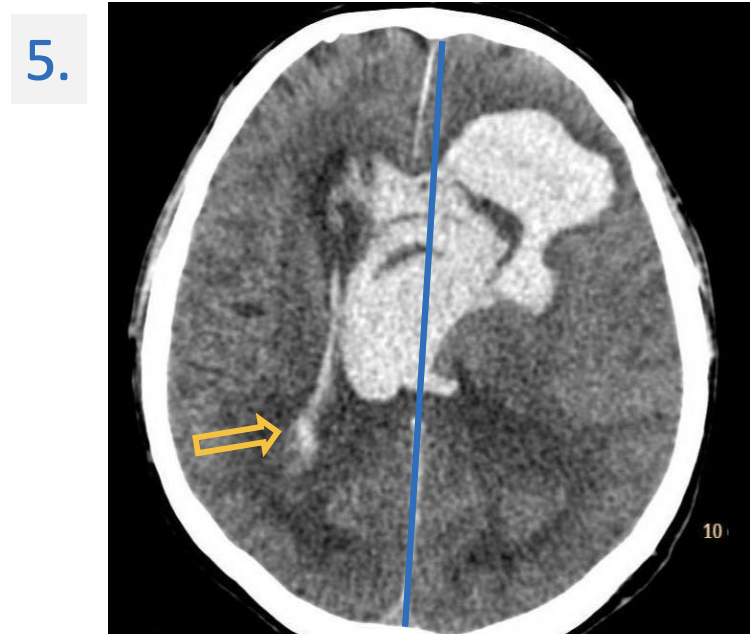

5.

apoplexy : unconsciousness or incapacity resulting from a cerebral haemorrhage or stroke.